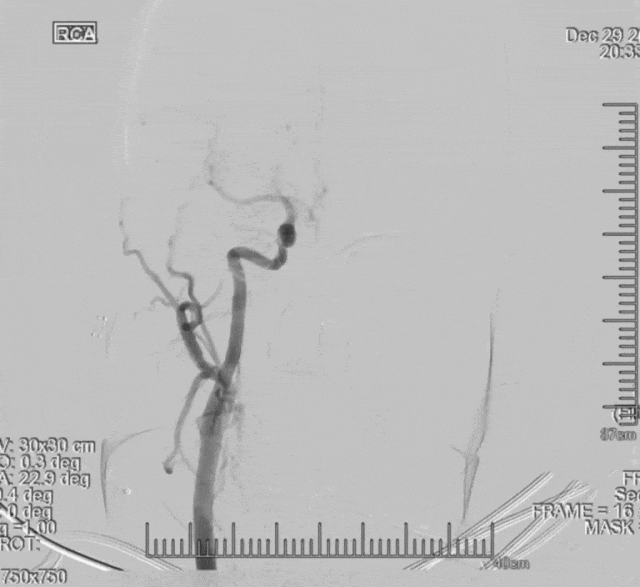

术前造影:左侧椎动脉V3段夹层,长度约37mm,基底动脉起始部以远未显影,双侧后交通开放,基底动脉未见造影剂充盈、返流。

左侧后循环

右侧后循环

左侧前循环

右侧前循环